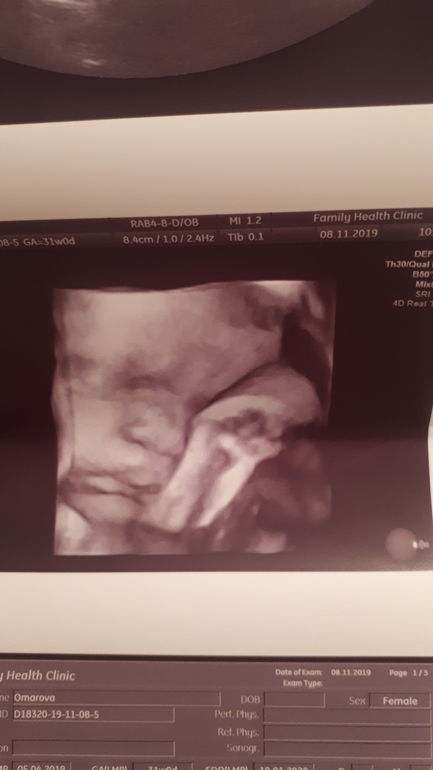

3D узи, г Атырау, Фамили клиник

На сроке 31 неделя сделали долгожданное 3д узи, хотелось посмотреть на своего малышонка 😁

Знакомство с малышонком прошло отлично, все показатели в норме, врач прекрасная женщина.

Оставлю фото на память 😋